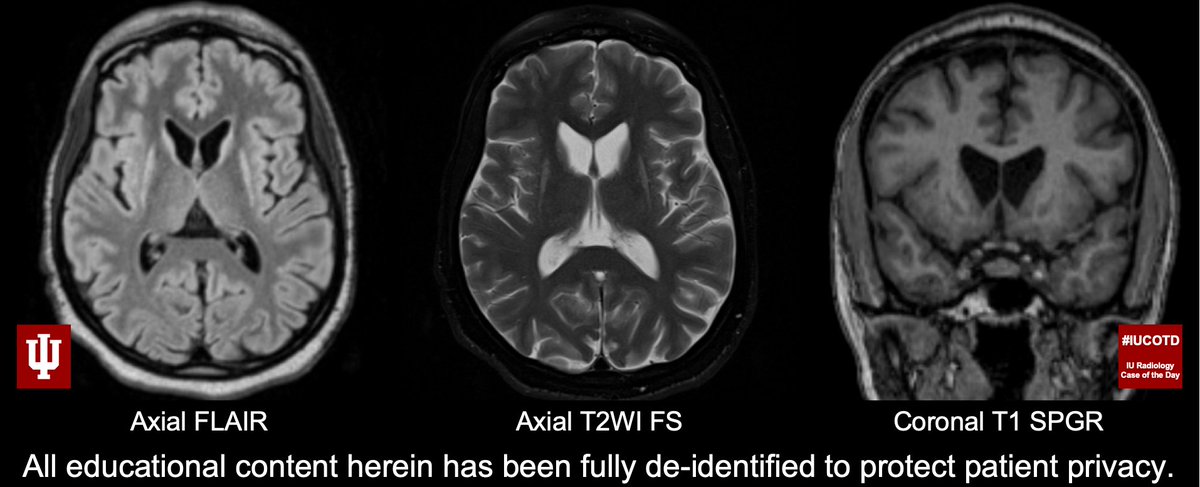

#IUCOTD #192 ANSWER: Huntington disease (juvenile onset)! CAG trinucleotide repeat. Terrible disease, poor prognosis. Thx@apkamer for case!#FOAMrad#RadRes#MedEd#NeuroRad#Radiology Learn more: https://youtu.be/n_Ecx_e1jSU@IURadiology#IUCOTD#YouTube: https://bit.ly/2EXkWnX pic.twitter.com/vWvQPXIPI7

#IUCOTD #192: Young man, gait & behavior disturbance. Findings? Diagnosis? Thx@apkamer 4 sharing case!#FOAMRad#RadRes#MedEd#NeuroRad#radiology Answer w/ appropriate GIF ONLY - stay professional & don't spoil answer!@IURadiology#IUCOTD#YouTube: https://bit.ly/2EXkWnX pic.twitter.com/cPylQjuwfY